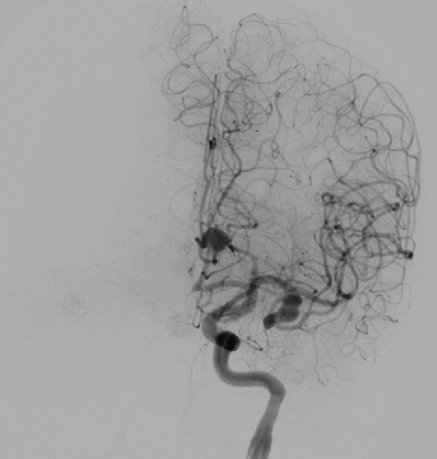

Preoperative Evaluation

Preoperative angiography revealed a shared trunk of bilateral anterior cerebral arteries, with a saccular aneurysm (8 mm × 6 mm) on the left anterior cerebral artery, a recurrent aneurysm (9 mm × 5 mm) on the left middle cerebral artery, and a wide-neck aneurysm (8 mm × 8 mm) on the right posterior communicating artery.

3D imaging of the left internal carotid artery

Anterior-Posterior view of the left internal carotid artery

Angiography of the right internal carotid artery